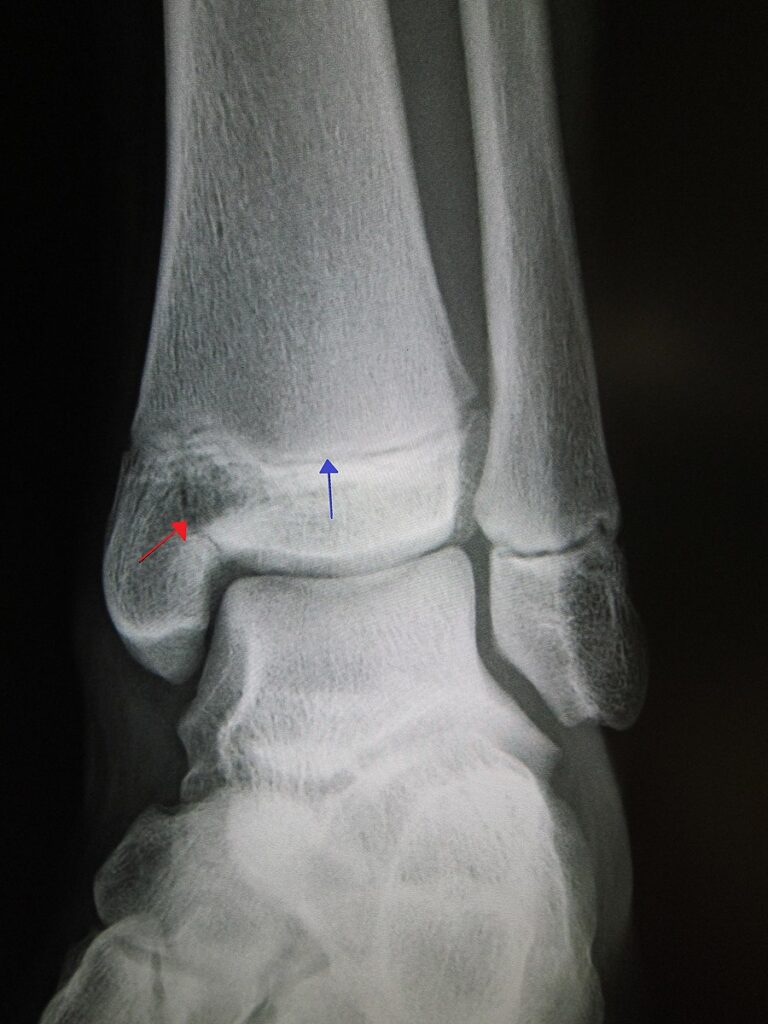

Example 2

Diagnosis

Salter-Harris Fracture

Image 2:James Heilman, MD, CC BY-SA 3.0 <https://creativecommons.org/licenses/by-sa/3.0>, via Wikimedia Commons